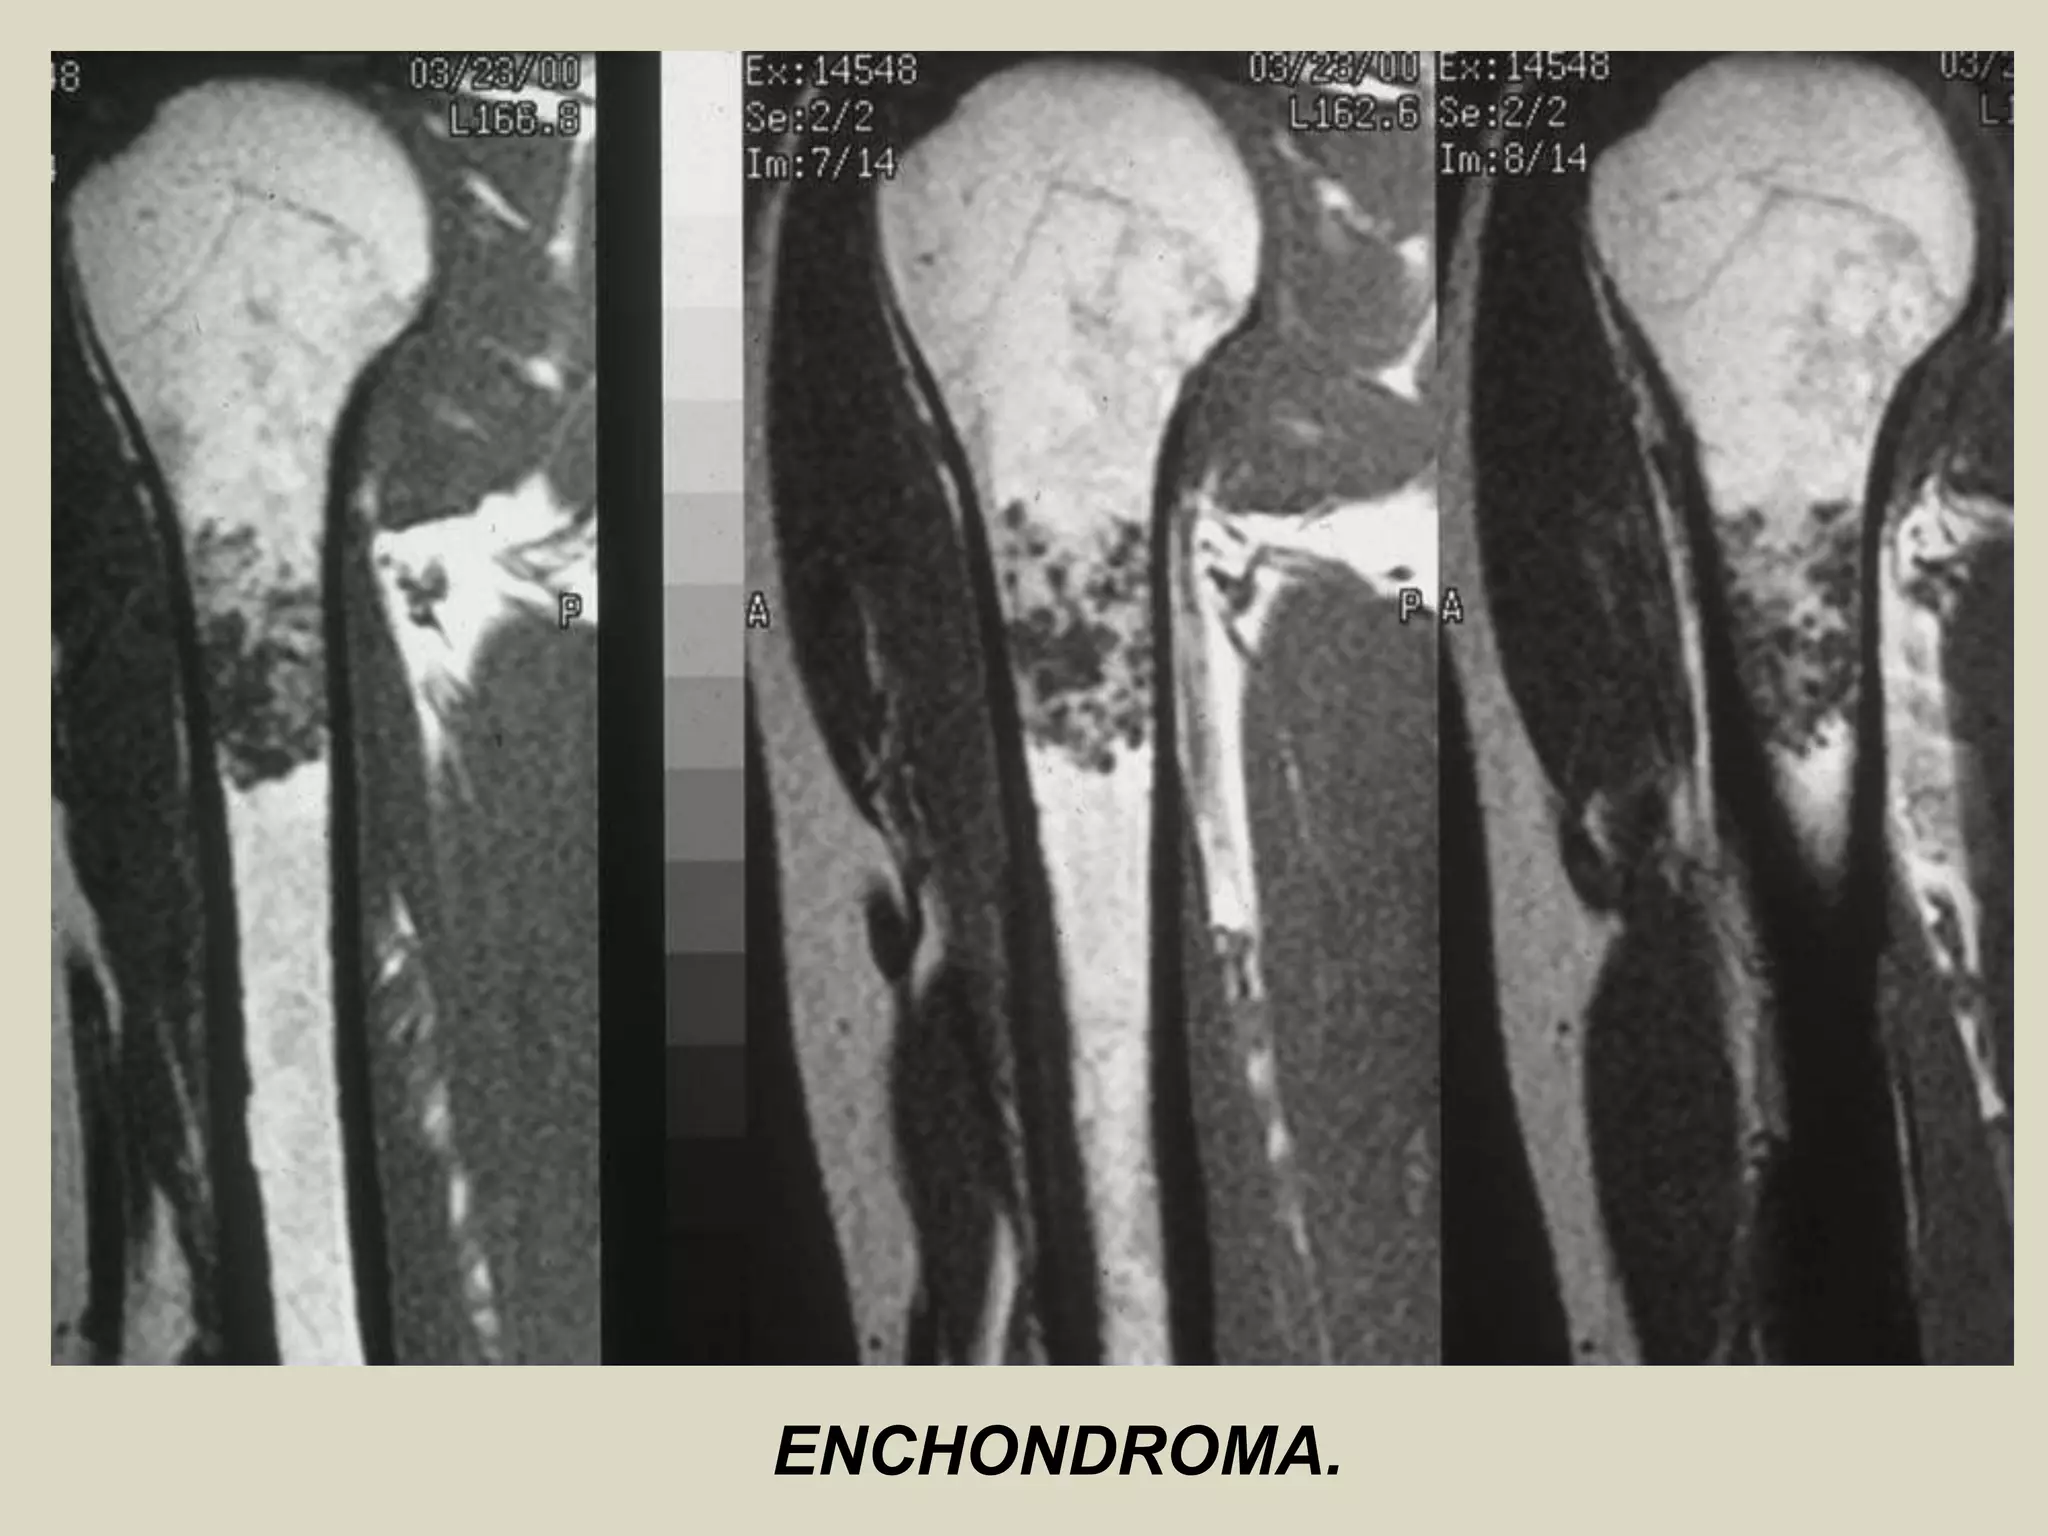

ENCHONDROMA AND ENCHONDROMATOSIS

Definition: Benign hyaline cartilage neoplasm of medullary bone.

Imaging:

- Well marginated tumors that vary from radiolucent to heavily mineralized.

- Mineralization pattern is characteristic, consisting of punctate, flocculent, or ring and arc pattern.

- Long bone tumors are usually centrally located within metaphysis.

- Diaphyseal long bone tumors are less common, and epiphyseal tumors are rare.

- Enchondromas in the small tubular bones can be centrally or eccentrically located, and larger tumors may

completely replace medullary cavity.

- More extensive endosteal erosion is considered suspicious for low grade chondrosarcoma.

- Cortical destruction and soft tissue invasion should never be seen in enchondromas and would be most

consistent with chondrosarcoma.

ENCHONDROMA.